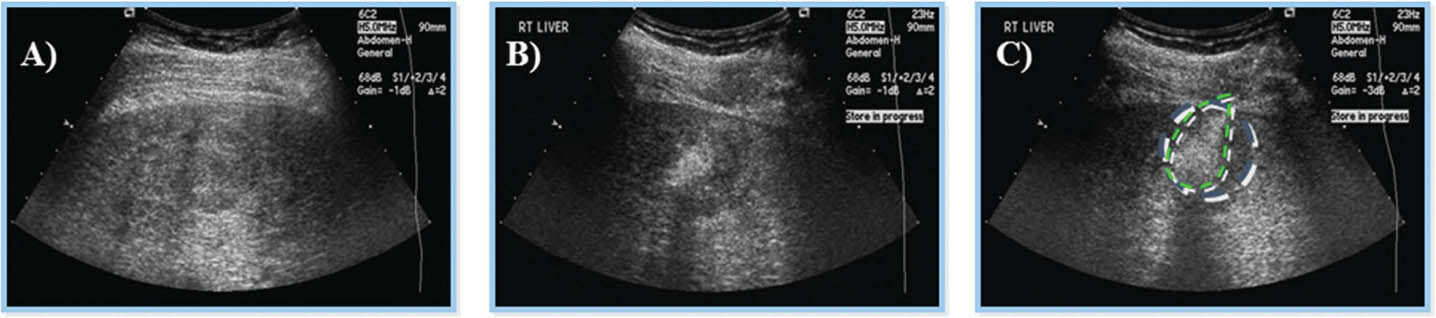

Percutaneous ethanol injection

Percutaneous ethanol injection (PEI) involves the imaging guided injection of ethanol into the tumor to induce coagulation necrosis (Figure 8) (66, 72). The non-subcapsular, non-perivascular nodules <2 cm are ideal for PEI because of its limited capacity to penetrate the tumor beyond its pseudo-capsule or fibrotic septa (60, 72). Although it is a cost-effective form of therapy, the recurrence tumor rate is higher when compared to other locoregional therapies, thus PEI has fallen into disfavor as the first line therapy for small HCC lesions. PEI has a recurrence-free survival rate of 77% at one year as compared to 86% in patients treated with radiofrequency ablation (RFA) (64). Its side effects include post procedural pain, and it requires several sessions to yield complete treatment (66).

Fig 8

Figure 8. Ultrasound-guided percutaneous alcohol injection of hepatocellular carcinoma. A and B. Under image-guidance by US, administration of ethanol (97%) is performed into the tumor. C. Noting an enlarging hyperechoic signal. Although the procedure in well-trained hands is reliable and practical for large scale application, malignant recurrence rates are high.